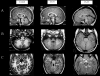

Joubert syndrome (JS) is an autosomal recessive disorder characterized by cerebellar vermis hypoplasia associated with hypotonia, developmental delay, abnormal respiratory patterns, and abnormal eye movements. The association of retinal dystrophy and renal anomalies defines JS type B. JS is a genetically heterogeneous condition with mutations in two genes, AHI1 and CEP290, identified to date. In addition, NPHP1 deletions identical to those that cause juvenile nephronophthisis have been identified in a subset of patients with a mild form of cerebellar and brainstem anomaly. Occipital encephalocele and/or polydactyly have occasionally been reported in some patients with JS, and these phenotypic features can also be observed in Meckel-Gruber syndrome (MKS). MKS is a rare, autosomal recessive lethal condition characterized by central nervous system malformations (typically, occipital meningoencephalocele), postaxial polydactyly, multicystic kidney dysplasia, and ductal proliferation in the portal area of the liver. Since there is obvious phenotypic overlap between JS and MKS, we hypothesized that mutations in the recently identified MKS genes, MKS1 on chromosome 17q and MKS3 on 8q, may be a cause of JS. After mutation analysis of MKS1 and MKS3 in a series of patients with JS (n=22), we identified MKS3 mutations in four patients with JS, thus defining MKS3 as the sixth JS locus (JBTS6). No MKS1 mutations were identified in this series, suggesting that the allelism is restricted to MKS3.